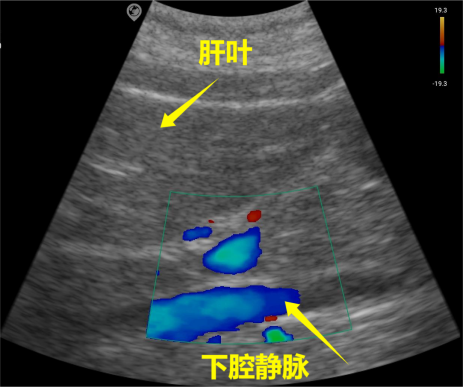

SonoMaxx Handheld Ultrasound MX6 for Inferior Vena Cava Scanning

Solid organs such as the liver, kidney, spleen, and pancreas exhibit isoechoic properties, with variations in echo intensity among different solid organs.